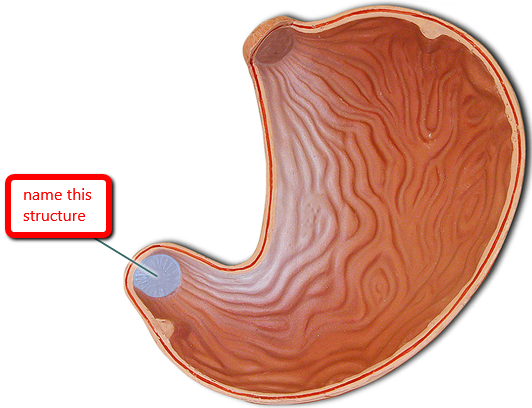

Body (of stomach)

Cardia (of stomach)

Fundus (of stomach)

Gastroesophageal sphincter

Pyloric Sphincter

Pylorus (of stomach)

Rugae (of stomach)